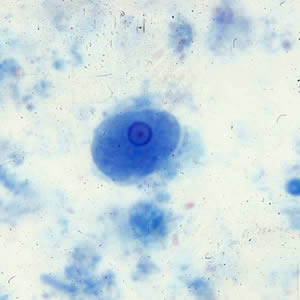

E.nana cysts

four nuclei. centrally karyosome only visible in trichrome stain